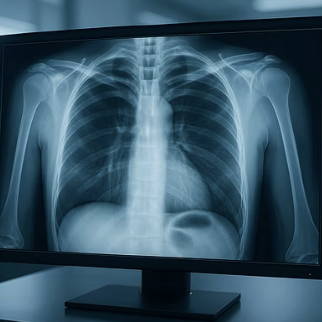

가까운 '호흡기내과'나 '가정의학과', '내과'를 방문하면, 간단한 흉부 X-ray 촬영과 청진만으로도 대부분의 원인을 감별해 낼 수 있습니다. 조기 진단이야말로 더 큰 병으로의 진행을 막는 가장 확실한 길입니다.